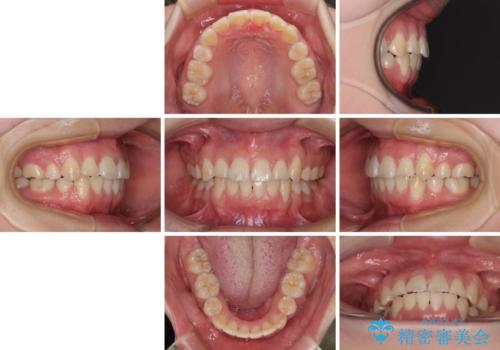

前歯が磨きにくい 目立たないワイヤー装置による矯正治療

- 上下前歯の叢生と八重歯を気にして来院された患者様です。

前歯部叢生のスペースを獲得するため、上下顎左右小臼歯各1歯を抜歯することとしました。

歯列はきれいに整いますが、歯肉ラインは治療前の歯肉の位置を踏襲します。

特に八重歯であった歯は歯冠が長く見えますので、改善を希望される場合には、歯肉移植術を行う必要があります。